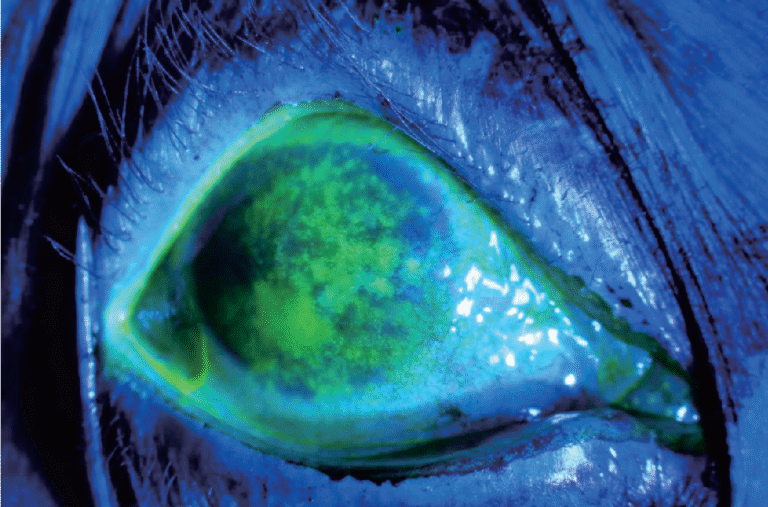

Integrated Filters

Built-in Yellow Filter

The PSL-9000 features a built-in yellow barrier filter that works in combination with cobalt blue illumination to reveal sodium fluorescein staining patterns on the cornea and ocular surface with exceptional clarity.